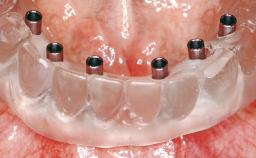

A 63-year-old male patient was referred for a consultation and treatment of partial edentulism in the maxilla. The patient presented with residual anterior teeth and declined a partial removable prosthesis. He reported that the maxillary posterior teeth had been extracted due to mobility and periodontal disease two months before the consultation. The patient’s chief complaint was that his residual maxillary teeth were mobile and that he was unable to chew. The patient’s desire was a stable and comfortable fixed maxillary rehabilitation. The patient was a light smoker (fewer than 10 cigarettes/ day), and his medical history was without significant findings. He was not on any regular medication at the time of consultation. The extraoral examination revealed a normal physiognomy with a correct distribution of the facial thirds. The patient presented a low lip line, and the transition line between teeth and soft tissues was not exposed during a forced smile.

| # of Implants | 6 |

| Attachment | One-Piece |

| Modality | 6+ implants with immediate loading |

| Loading Protocol | Immediate |